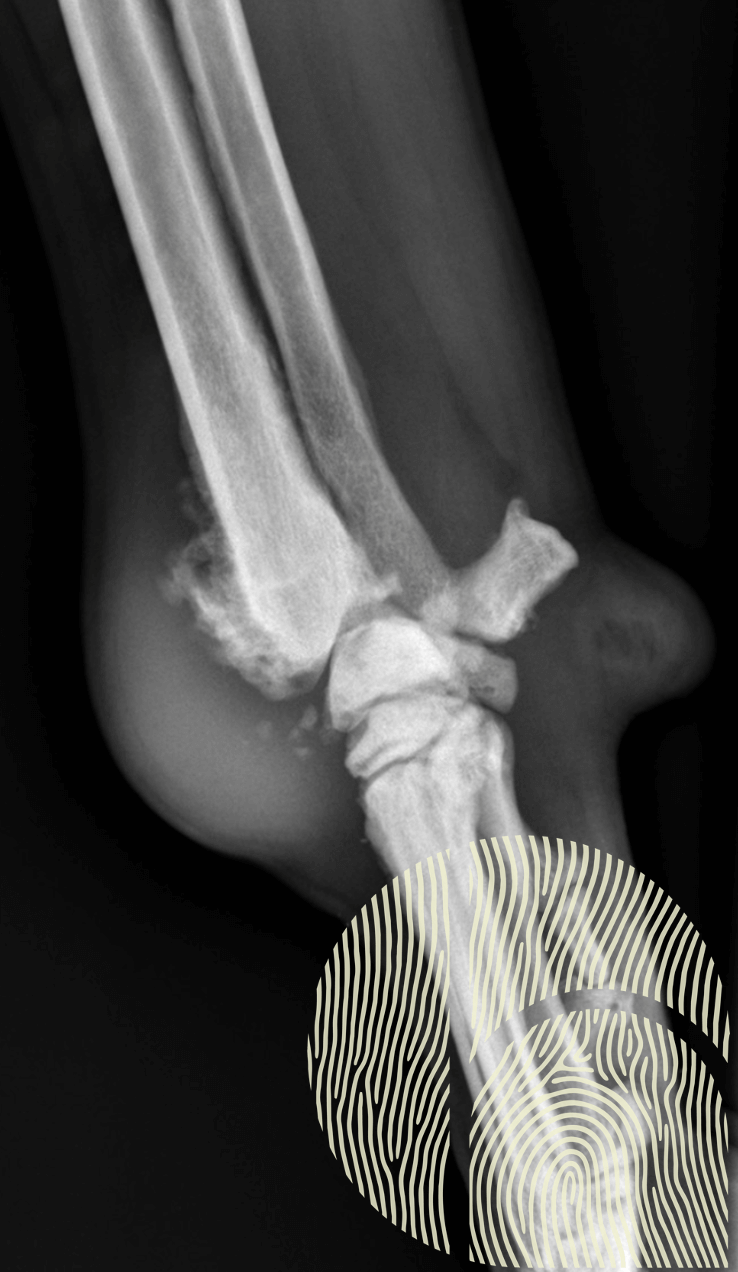

Un diagnostic précis repose sur une combinaison d’examen clinique et d’imagerie. Les radiographies et le scanner permettent de visualiser un gonflement des tissus mous et, dans certains cas, une prolifération osseuse sur la face médiale du radius distal. La ténosynovite du LAP peut être bilatérale, rendant l’examen des deux membres essentiel.

Radiographie de profil du carpe : Tuméfaction sévère des tissus mous et prolifération osseuse sur le radius distal.